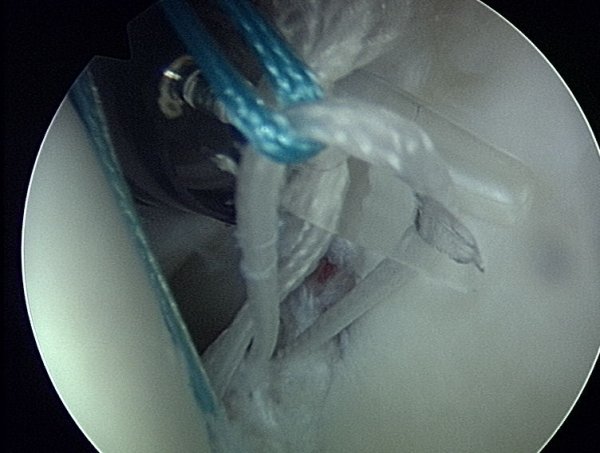

" Naciąganie opony " czyli umieszczenie obrąbka na panewce w anatomicznej pozycji. Przyczepianie obrąbka odbywa się przy pomocy tzw. kotwiczki, ktorą może być z metalu lub biowchłanialna.

Przykład kotwicy biowchłanialnej